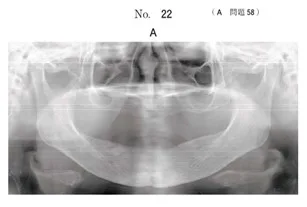

65歳の男性。右側顎下部の腫脹を主訴として来院した。

2年前から同部の腫脹と消退を繰り返していたがそのままにしていたという。

腫脹部は限局性で、軽度の圧痛を認める。

初診時のエックス線画像(別冊No.22A)とCT(別冊No.22B、C)を別に示す。

手術に際し切開するのはどれか。1つ選べ。